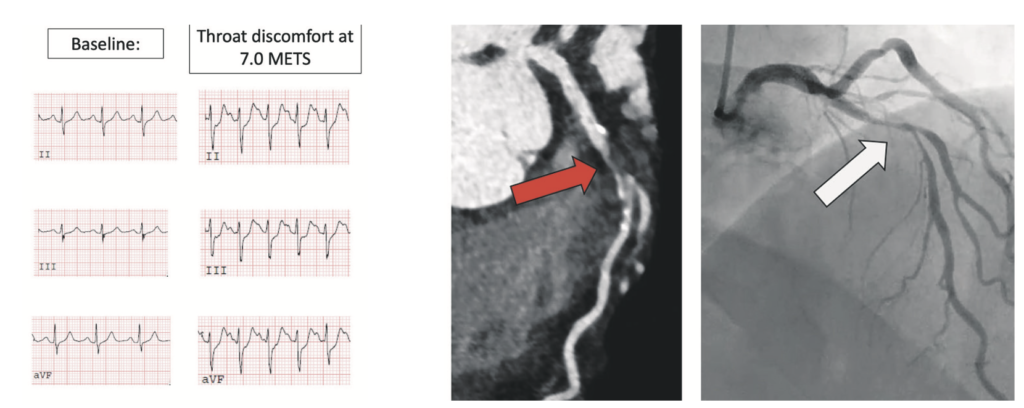

The patient was initially referred for ETT. This was submaximal and stopped as he developed chest and throat discomfort at 7.0 METS, having not achieved 85 per cent of his age-predicted maximal heart rate. There was upsloping ST depression in the inferior leads, which are non-diagnostic ECG changes. He was keen to avoid ICA and so was referred for CTCA. This showed a large amount of mostly non-calcified plaque in the proximal left anterior descending (LAD) artery, extending into the mid LAD and resulting in severe stenosis (70-to-99 per cent) proximal to the origin of the first diagonal vessel. ICA was then performed, confirming severe stenosis of the proximal and mid LAD, and the patient underwent successful PCI to the LAD (see Figure 2). In this case, the CTCA identified the cause of his symptoms in a prognostically-significant location in the LAD.